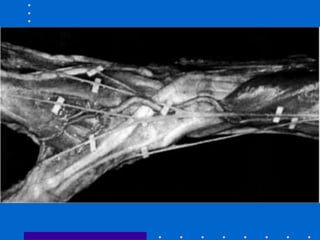

Fixação externa + Pinagem

• Aumenta estabilidade e previne perda de

redução com relação ao FE isolado

• Maior complicação é lesão do nervo radial

superficial

• Fazer incisão de 5 mm e utilizar

hemostática para liberar trajeto

• Colocar fig 26 19 1

• Figura 26-21